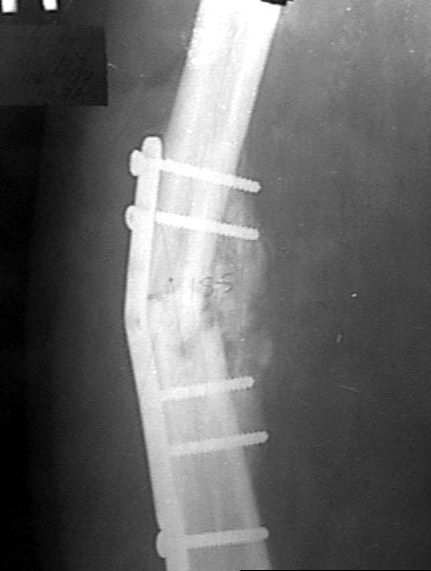

Alexander Chelnokov 10 Апрель 2004, 19:37

1

2

Наконец, 23 марта сделали и голень.